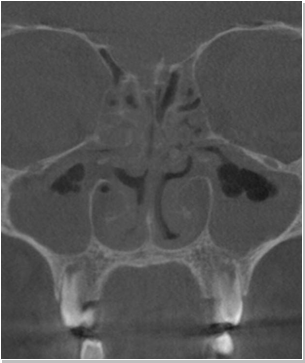

비염

비중격만곡증

축농증

비중격 연장술 후 비중격만곡증 재수술 가능할까요?비중격만곡증 질환 수술만 했을 경우 비중격만곡증 재수술이 가능합니...

코 성형 후 코막힘이 심한가요? 코 성형 부작용으로 코막힘 증상이 심해지거나 지속돼 생활에 불편함을...